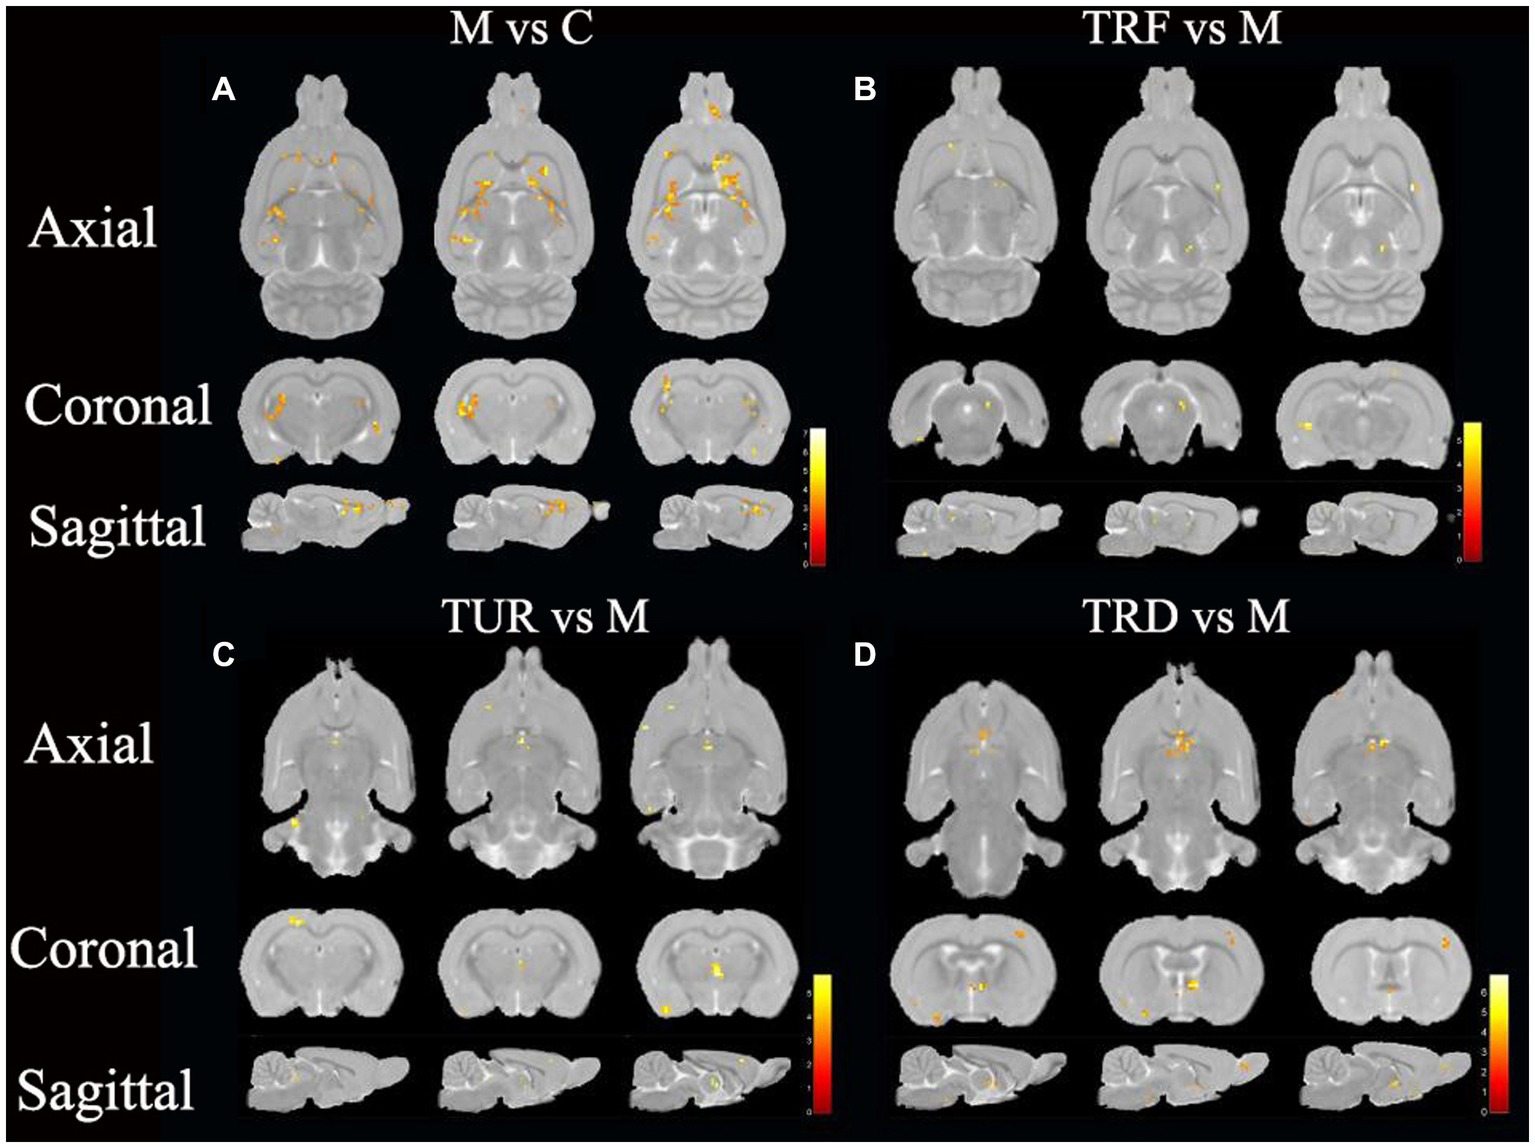

The brain regions with decreased ALFF in the model group compared to that in the control group were the hypothalamus (left), entorhinal cortex (left and right), hippocampal dentate gyrus (left and right), etc. (Figure 4A). The brain regions with increased ALFF in the TRF group compared to that in the model group were the cerebellum (left and right), striatum (right), primary motor cortex (right), etc. (Figure 4B). The brain regions with increased ALFF in the TUR group compared to that in the model group were the hypothalamus (left), basal forebrain region (right), primary visual cortex (left), etc. (Figure 4C). The brain regions with increased ALFF in the TRD group compared to that in the model group were the thalamus (left and right), olfactory bulb (left and right), brainstem (left and right), etc. (Figure 4D). The locations of brain regions with significant differences are presented in Supplementary Table S2.

Figure 4

ALFF difference brain regions map. (A) Brain regions with decreased ALFF in the model group versus the control group (M vs. C); (B) Brain regions with increased ALFF in the TRF group versus the model group (TRF vs. M); (C) Brain regions with increased ALFF in the TUR group versus the model group (TUR vs. M); (D) Brain regions with increased ALFF in the TRD group versus the model group (TRD vs. M). The color bars were used to signify the t-value of the group analysis (the color is brighter; the t-value is higher).

Similar to the ReHo analysis above, we focused on callback brain regions. Callback brain regions in the TUR group included the entorhinal cortex (right), corpus callosum (right), olfactory bulb (left), hypothalamus (left), etc. Callback brain regions in the TRF group included the entorhinal cortex (left), hippocampus (left), cerebellum (left and right), etc. Callback brain regions in the TRD group included the entorhinal cortex (left and right), hypothalamus (left), striatum (left and right), hippocampal dentate gyrus (left), etc.